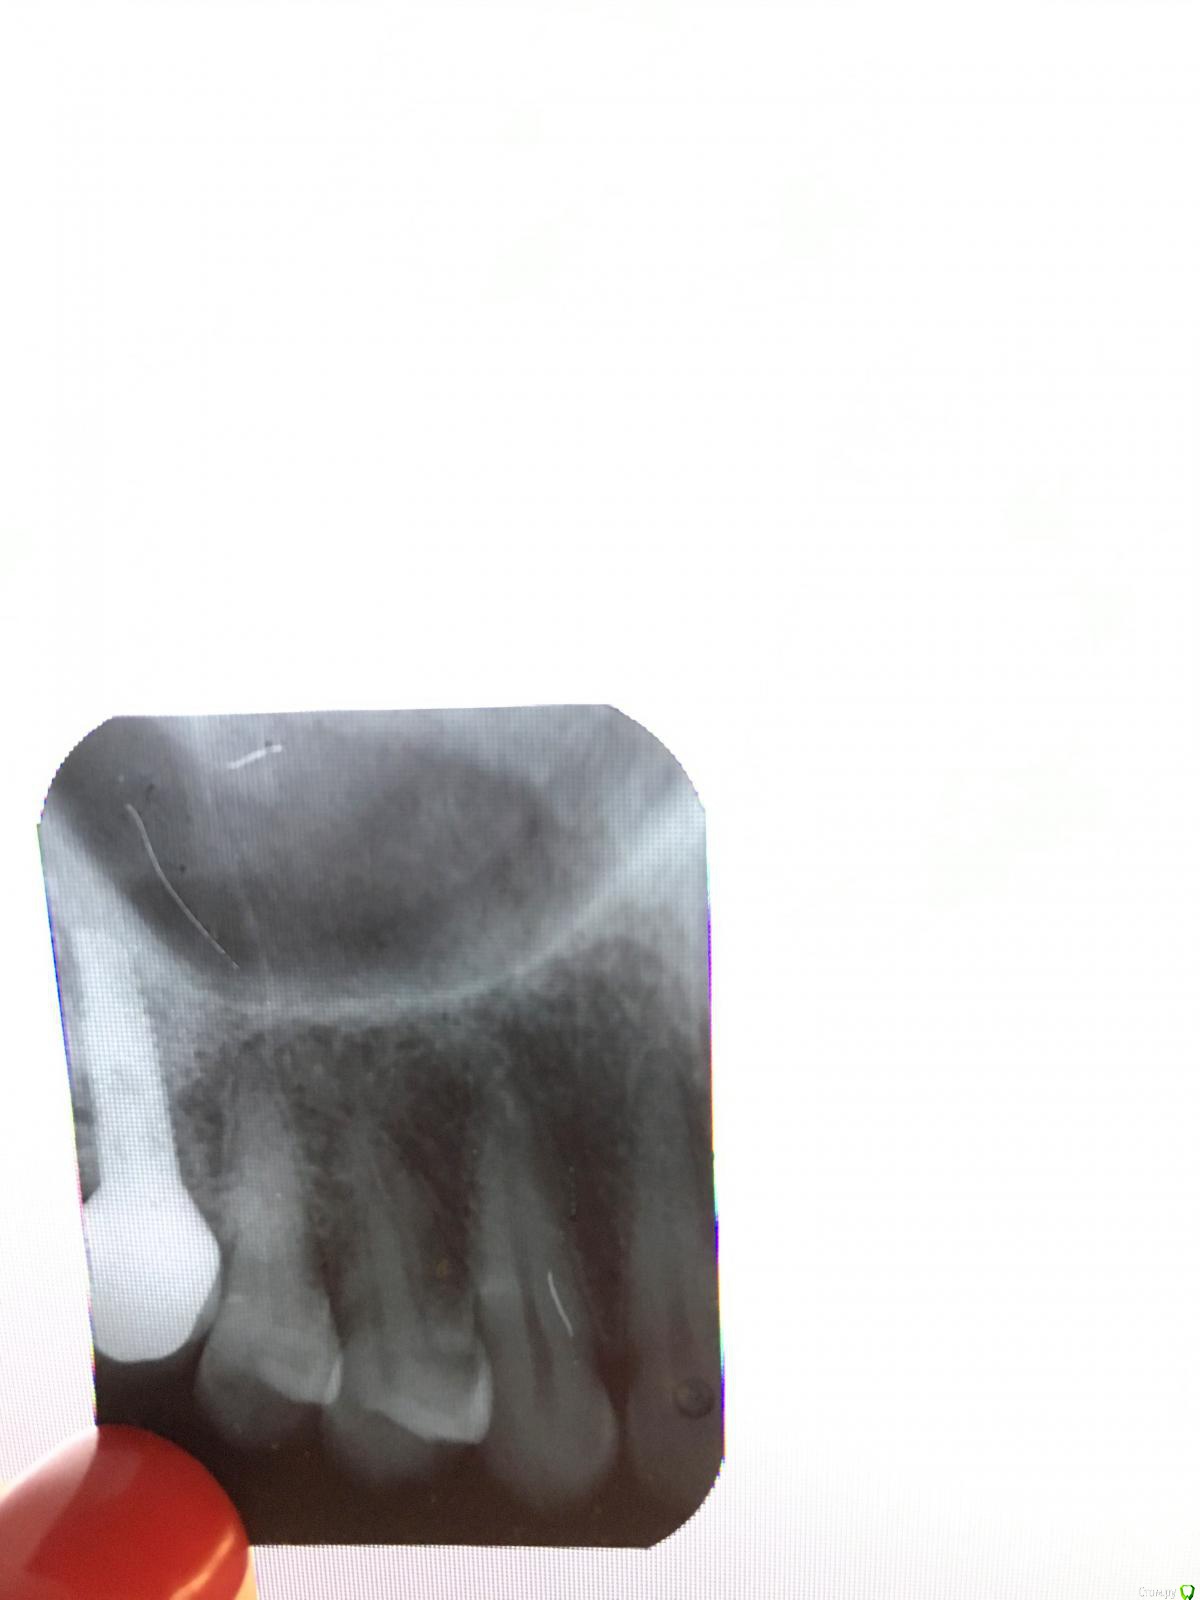

Ольгаxxx Опубликовано 2 декабря, 2019 Автор Поделиться Опубликовано 2 декабря, 2019 Здравствуйте, ув. врачи! Обошла несколько стоматологий, ни в одной нет визиографа((((. Пришлось сделать еще один прицельный. Помогите, советом, пожалуйста, завтра к стоматологу, а я не знаю, как убедить его, что у меня там кариес (а может его там и нет), но напомню, что была реакция на сладкое. Не постоянно, но периодами как-то. Врач кариеса не видит визуально. Очень буду ждать вашего совета. Спасибо. Ссылка на комментарий

ЛанаМ Опубликовано 3 декабря, 2019 Поделиться Опубликовано 3 декабря, 2019 Не всегда на рентгене четко виден кариес, особенно если он небольшой. Лучше сочетать рентген и очный осмотр. Если доктор сомневается в наличии кариеса, лучше подождать. Чувствительность к температурным и химическим раздражителям еще дают абфракции - это сколы эмали в области шейки зубов. Проверьте у доктора их возможное наличие. Ссылка на комментарий